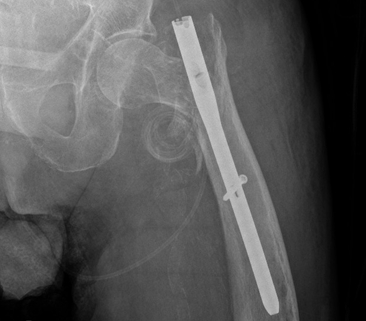

一名 85 岁男性因左股骨转子间骨折接受了短头髓钉固定术。跌倒后,检查显示头髓螺钉从内侧上移位到盆腔中。血管造影显示螺钉尖端位于髂骨分叉处 2 厘米以内,没有出血或内脏损伤的证据。

术后X线片